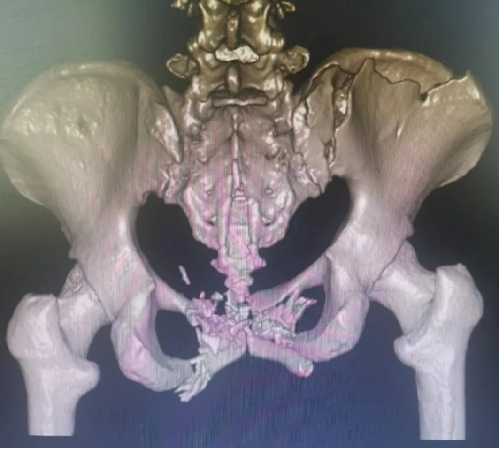

患者黃(huáng)某,因車禍外傷導致全身多處疼痛入院(yuàn),入院即因失血性休(xiū)克於ICU監(jiān)護,完善檢查顯示雙側恥骨粉碎性骨折、右側髂骨多處骨折、右骶髂關節脫位,提示骨盆前-後環均不穩定(dìng)。

對於此種前後環均嚴重失穩(wěn)的複雜(zá)骨盆(pén)骨折的治療,保守治療不僅需長期臥床,易導致褥(rù)瘡、肺部感染、泌尿(niào)係(xì)感染及深靜脈血栓風險,同時勢必影響後(hòu)期功(gōng)能恢複,嚴重降低患者未來生活質量。傳統開放術式手術切口大、手(shǒu)術時間長,手術難度極大,同時存在盆腔內血管神經及膀胱的醫源性損傷風險,以往,遇到此種嚴重(chóng)病情隻能依賴上級醫院專家來(lái)院手術指導,但基於(yú)近期成功開展的骨盆微創治療的經驗支持,外一科董(dǒng)明主任反複(fù)研究患者病情及影像,充(chōng)分(fèn)考慮手術創傷與(yǔ)風險後,決定開展(zhǎn)骨盆骨折(shé)有限切開複位(wèi)內固定術。

經充分術(shù)前準備,由董明主(zhǔ)任、餘策略主(zhǔ)治醫師、葉強醫(yī)師為患者在全麻下僅用不到2小時便成功完成了手術,術中(zhōng)出血量少,術後第二天患者(zhě)就可以床(chuáng)上坐起及翻身,功能恢複良好。